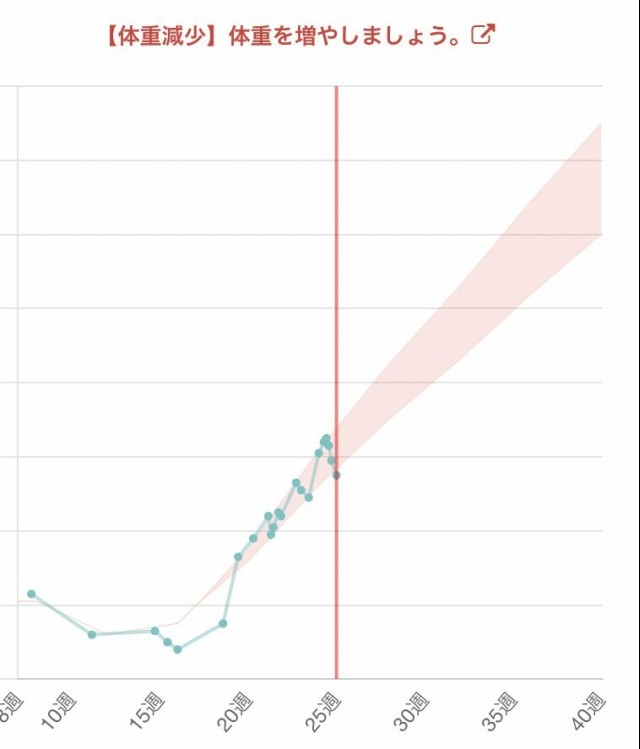

体重管理 28w0d 推定体重1277g 体重+600g(妊娠前+2.1kg) 今日はお顔見せてくれた♡? 相変わらず唇ぷっくりしてる? そして帝王切開の予定が1日早まったから予定日変わったw

体重管理 ねぇ私の体どうなってんのホンマに? このアプリに先週は体重増加、妊娠高血圧症に注意って言われて 今日は体重を増やしましょうって(°᷄д°᷅) 妊婦の体重管理ムズすぎる… 毎日同じように食べて同じ時間帯に測ってるのに こんなギッザギザに上下してる人居てるんかな…?